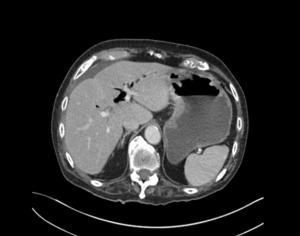

A 92-year-old man presented to emergency with abdominal pain, vomiting and fever. He had been experiencing 24 hours of abdominal pain which had become significantly worse in the last 3 hours. He has generalized abdominal tenderness and distention. Lactate is 2.5 and he has a mild AKI.

EXPLANATION -There are multiple dilated loops of small bowel secondary to small bowel obstruction. There is mild mural thickening in the right lower quadrant, suggestive of early ischemia. An abrupt transition is seen in the terminal ileum due to a 30 mm gallstone – a gallstone ileus.

Pneumobilia is present, this is secondary to a cholecystoduodenal fistula.

Gallstone ileus is an uncommon but potentially serious cause of small bowel obstruction.

- It occurs when a gallstone enters the small bowel via a biliary-enteric fistula, causing a mechanical bowel obstruction.

- The site of obstruction is the terminal ileum in 50-70% cases (as in this case), 90% of stones over 2cm in diameter cause obstruction. There may be colicky, often periumbilical, abdominal pain, distension, constipation, nausea and vomiting.

- Current surgical options are simple enterolithotomy (as in this case); enterolithotomy, cholecystectomy and fistula closure (one-stage procedure) or enterolithotomy with cholecystectomy performed later as a two-stage procedure.

- This patient went for urgent laparotomy. A 3cm gallstone was found in the distal ileum. The gallstone was able to be moved proximally, and an enterotomy was performed for removal of the gallstone via the ileum.